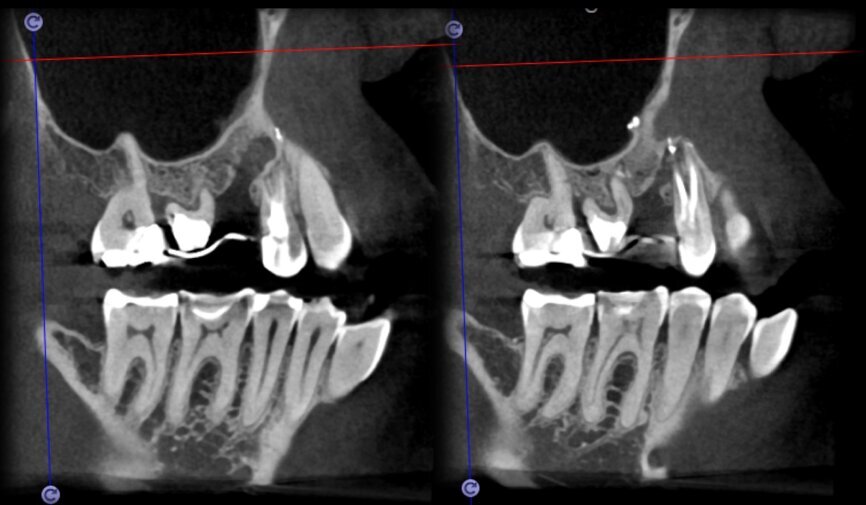

The case with which I would like to start my clinical review is a perfect example of how difficult it is to establish the origin of the patient’s symptoms on the basis of an intraoral radiograph alone. Not only does the 2D study fail to establish with certainty the presence of a lesion, but more importantly, it is impossible to establish the size, morphology and type of the lesion. An analysis of the 3D imaging, however, provides a clear picture of the clinical situation: the coronal and sagittal slices revealed the presence of a large lesion extending from the apex of the mesial root of this molar to the furcation, while the axial slices allow us to conduct a precise analysis of the endodontic anatomy and, in particular, the shape of the mesial root, which in this case was fused with the palatine root. A full overview of the case can, therefore, guide the decision-making process and direct the treatment plan towards a specific type of treatment (Figs. 1–4).